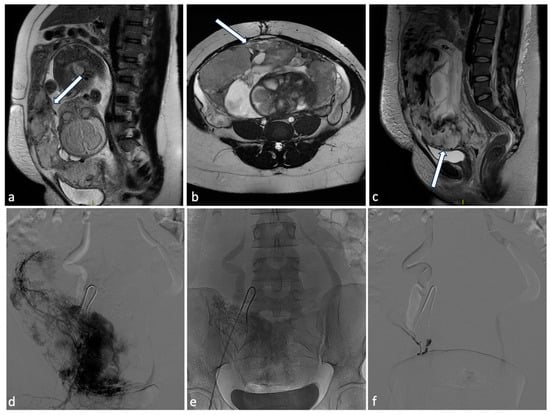

Figure 9.

Placenta percreta. A 38-year-old woman at 27 weeks of gestation with placenta previa percreta. Sagittal (a) and axial (b) T2W SSFSE images show a heterogeneous placental signal with some low signal intensity bands representing venous lakes (arrows). There is also a focal uterine bulge with thinning of the overlying myometrium. The patient underwent a caesarean section and extraction of the fetus but no secondment due to placenta percreta. In the post-partum MRI (c), signs of placental percreta were still present with an image of bladder infiltration (arrow), later confirmed at cystoscopy. It was decided to perform endovascular devascularization of the placenta percreta left in situ before proceeding to hysterectomy. Preliminary arteriography of the abdominal aorta documented hypertrophy of both uterine arteries, clearly greater on the right, which exuberantly vascularized the hypertrophied placenta, supplying multiple intraplacental high-flow vascular lakes (d). After superselective catheterization with a coaxial microcatheter of both uterine arteries and some of their distal branches, bilateral embolization was performed by infusion of a suspension of embolizing particles. The procedure was completed with release of 3 platinum microspirals (3 mm diameter) at the level of the distal right uterine artery (e), proximal to the origin of the main collaterals and 2 microspirals (3 mm) at the origin of the left uterine artery. At the end of the operation, satisfactory uterine and placental devascularization was shown (f).